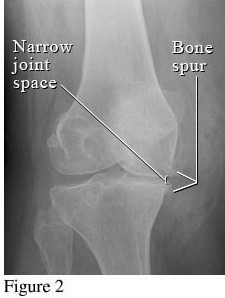

2. Giai đoạn 2: Thoái hóa khớp gối độ 2

Hình ảnh của khớp gối trên phim X-quang: Khe khớp hẹp nhẹ, có gai xương nhỏ.

Giai đoạn 2 vẫn được xem là giai đoạn tiến triển nhẹ, xem trên phim X-quang có thể thấy kích thước bề mặt sụn khớp vẫn chưa có sự thay đổi nhiều. Bao hoạt dịch khớp vẫn hoạt động bình thường, cung cấp đủ dịch khớp để nuôi dưỡng sụn và bôi trơn ổ khớp, giúp các đầu xương hoạt động được trơn tru. Mặc dù vậy, bệnh nhân vẫn có thể xuất hiện một số triệu chứng như đau mỏi ở khớp gối sau khi vận động nhiều hoặc khi làm việc quá sức, làm việc sai tư thế; cứng khớp khi trời lạnh hoặc do ít vận động khớp.

3. Giai đoạn 3: Thoái hóa khớp gối độ 3

Hình ảnh của khớp gối trên phim X-quang: Khe khớp hẹp rõ, nhiều gai xương kích thước vừa, đặc xương dưới sụn, đầu xương có thể bị biến dạng.

Thoái hóa khớp gối tiến triển đến giai đoạn 3 thì bệnh nhân sẽ càng cảm nhận rõ những cơn đau tại khớp gối. Các lớp sụn khớp bao bọc các đầu xương bị bào mòn nhiều và khoảng không gian giữa các đầu xương bị thu hẹp thấy rõ. Khả năng đi bộ của người bệnh giảm, đi, đứng, ngồi xổm, lên xuống cầu thang cũng thấy đau. Tình trạng cứng khớp vào buổi sáng cũng xảy ra thường xuyên hơn kèm theo các đợt viêm khớp gối (sưng, đau, tràn dịch) hoặc có biểu hiện vẹo khớp gối.